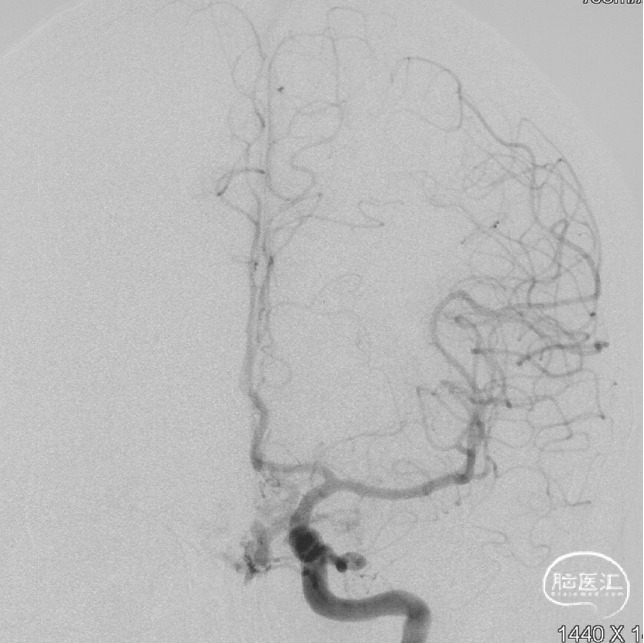

最终造影瘘口完全不显影。

Onyx胶铸型进一步显示了瘘的结构。AFA:镰前动脉;AEA:筛前动脉;PEA:筛后动脉;DV:引流静脉。

术后三个月造影复查,双侧颈内动脉、颈外动脉造影均未见静脉早显,DAVF治愈。